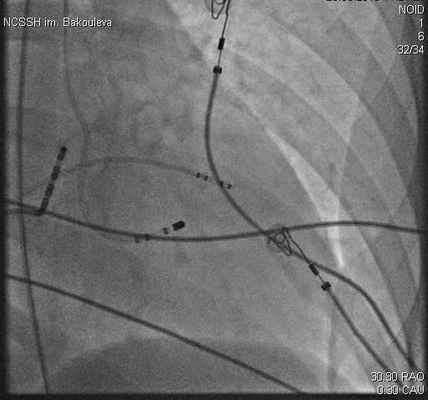

Программируемая стимуляция из области верхушки ПЖ одиночными (15 пациентов), парными (2 пациента) или тройными (5 пациентов) экстрастимулами индуцировала тахикардию у 22 пациентов, учащающая стимуляция - у 2 пациентов (рис. 2). Учащающей предсердной стимуляцией ФТ вызывалась у 11 пациентов (41%), из них у одного пациента индукция ФТ при правожелудочковой стимуляции была неэффективной.

Таким образом, вышеописанным протоколом стимуляции удалось индуцировать пароксизм ФТ или частые фасцикулярные экстрасистолы и провести адекватное активационное картирование у 100% пациентов. У всех пациентов тахикардия купировалась с использованием программированной или учащающей желудочковой стимуляции (рис. 3).

Электроды доставляют в сердце и процедуру проводят под контролем рентгеноскопии (рис.2).

| Рисунок 1. РЧА очага желудочковой тахикардии при электрическом шторме | Рисунок 2. Rg-стоп кадр при выполнение РЧА очага ЖТ в ЛЖ, транссептальным доступом |